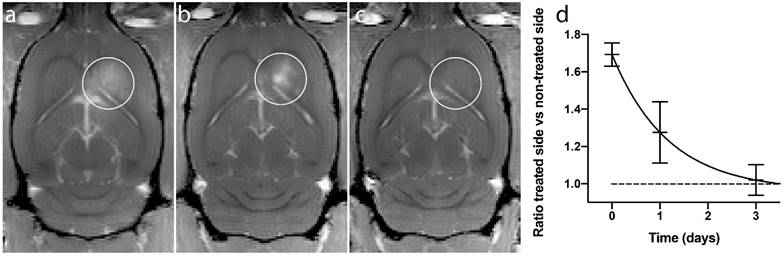

Figure 2

Comparison of gadodiamide signal intensities from MR-images. White rings indicate BBBD, (a) ACT+A+E, (b) ACT+A, (c) Sonazoid™ +A+E. (d) Scatter plot with mean and standard deviation. ** (p<0.01), *** (p<0.001).

ACT in combination with the activation and enhancement step clearly opened the BBB allowing MRI contrast agent to enter into the brain tissue (Fig. 2). Fig. 2 shows strong gadodiamide signal in the brain treated with ACT and activation and enhancement FUS, whereas only giving ACT and the activation FUS exposure showed hardly any signal. ACT was also much more efficient than the commercial Sonazoid in opening the BBB in combination with ultrasound. To obtain more quantitative data, the ratio of gadodiamide signal in the treated part vs. the non-treated contralateral part of the brain was calculated. In average, the ratio increased 50% for ACT+A+E treatment, compared to 18% for the Sonazoid™+A+E treatment (Fig. 2d). The extravasation of gadodiamide into the brain caused by ACT+A+E was significantly higher (p<0.01, Figure 2d) than with Sonazoid™+A+E (groups 1 and 4, respectively). ACT+A (group 2) caused similar gadodimamide extravasation as for Sonazoid™+A+E. ACT+E only (group 3) and Saline+A+E (group 5) did not induce BBBD and are thus not included in Fig. 2.

With the ultrasound activation and enhancement regimes applied, the ACT treatment clearly induced a significantly higher extravasation of gadodiamide to the brain than regular, small contrast microbubbles. Several important distinctions may contribute to this difference in effect level. The ACT-bubbles are in close contact with the endothelium over a significant segment of the vessel wall, ensuring a large interfacing area between the oscillating bubble and the endothelial cells. Sonazoid™, on the other hand, is free flowing and the average distance between the microbubble surface and the endothelial cells may limit the biomechanical effect level. ACT-bubbles are approximately 1000 times larger (by volume) than Sonazoid™ microbubbles and the biomechanical effects these large bubbles induce, even at low ultrasound pressures, should be orders of magnitude larger than with regular contrast microbubbles. Moreover, the lodged ACT-bubble will cause an increased microvascular pressure on the arterial side of the bubble and the induced transcapillary pressure gradient will enhance extravasation.

Comparing ACT+A with ACT+A+E, the 10 min, low MI enhancement step in the later treatment scheme is clearly increasing extravasation. Whether this is due to generation of larger openings with prolonged treatment, greater influx from longer treatment time, or a combination, cannot be determined from these experiments. Moreover, the enhancement step alone fails to produce BBBD with ACT, indicating that the phase shift event is a prerequisite for an effective BBBD.